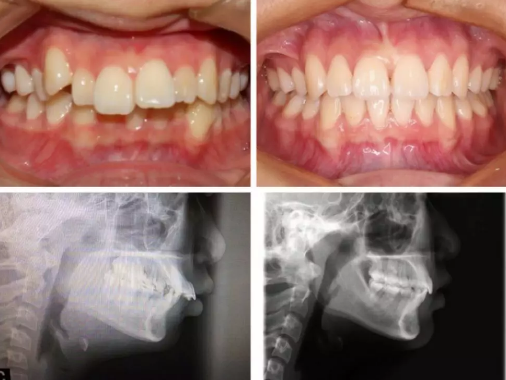

CASE 1

关键词

.牙齿拥挤、虎牙突出、过咬合.

这个牙挺乱的吧,虎牙突出,拥挤,深覆合,过咬合,这个是很多小伙伴都有的问题。看看看,这个case你们觉得够复杂吗?invisalign做到了,45个牙套,64周,16个月完成啦!

全头xray我们可以看到牙齿矫正前后侧面脸型和嘴型产生的变化。当然,由于她的过咬合非常严重(上下排差距太大),拔去了上牙的左右两颗第一前臼齿,能够把整个上排往后退并调整下排牙齿角度,使牙齿能够达到标准咬合。

幅 45 16 月